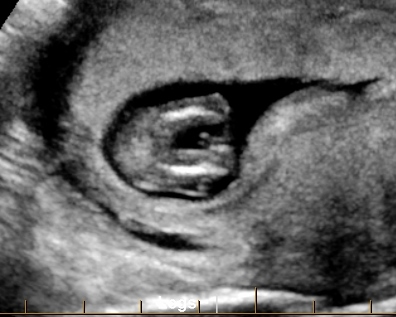

Potty shot looks girl but nub looks questionable

How many weeks is this? There is no hamburger in the first, and probably a penis in the second so I'm going for boy.

This was at 12w2d

Could definitely be either as it's a bit early for nub guessing